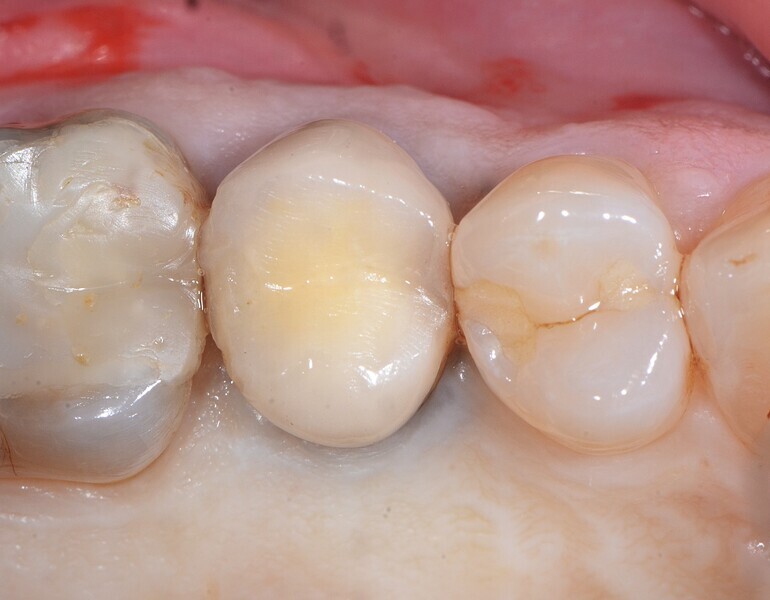

Fig. 24 : Photo montrant l’intégration tissulaire parfaitement réussie après deux mois.

La pose immédiate d’un implant deux pièces en céramique au niveau tissulaire a été accomplie tout en préservant l’alvéole (allogreffe constituée d’un substitut osseux et protection par une membrane de collagène résorbable). La mise en charge n’a pas été réalisée à ce stade (Figs. 12–24)